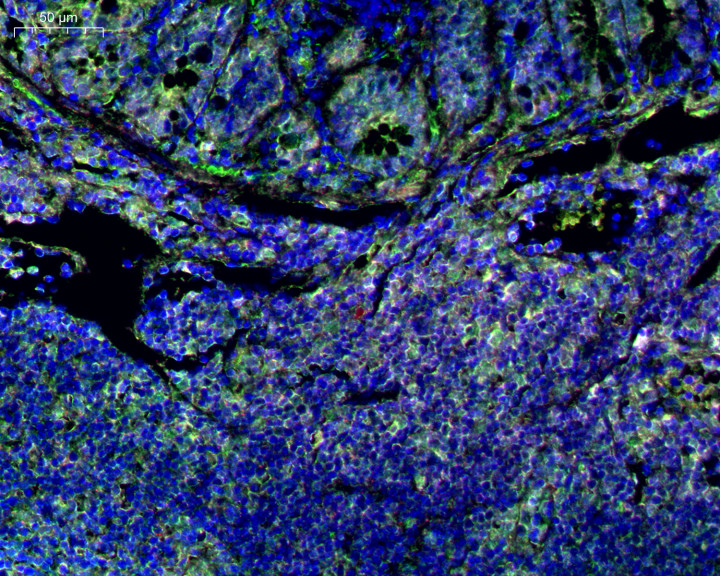

关于弱抒发抗原信号细小的问题,普拉特泽生物的TSA信号放大时期,能将细小信号放大10 - 50倍,小九体育在线直播官网让蓝本看不见的阳性细胞明显呈现。以PD - L1等免疫搜检点分子为例,老例免疫荧光简直检测不到信号,但使用普拉特泽生物的TSA试剂盒,就能精确捕捉到这些低品貌靶点,使检测成果更精确。

在多色符号方面,念念作念4色、5色以致7色多标免疫荧光时,统一物种抗体串色问题一直是个艰难。用传统标准反复优化抗体组合,消耗2个月也曾串色,审稿东说念主也会质疑共定位成果的确实性。普拉特泽生物的TSA时期遴荐酪胺千里积旨趣,抗体无需径直偶联荧光基团,透顶管束同物种抗体串色问题,扶持3色、4色、5色、7色多标,共定位成果确实可靠。